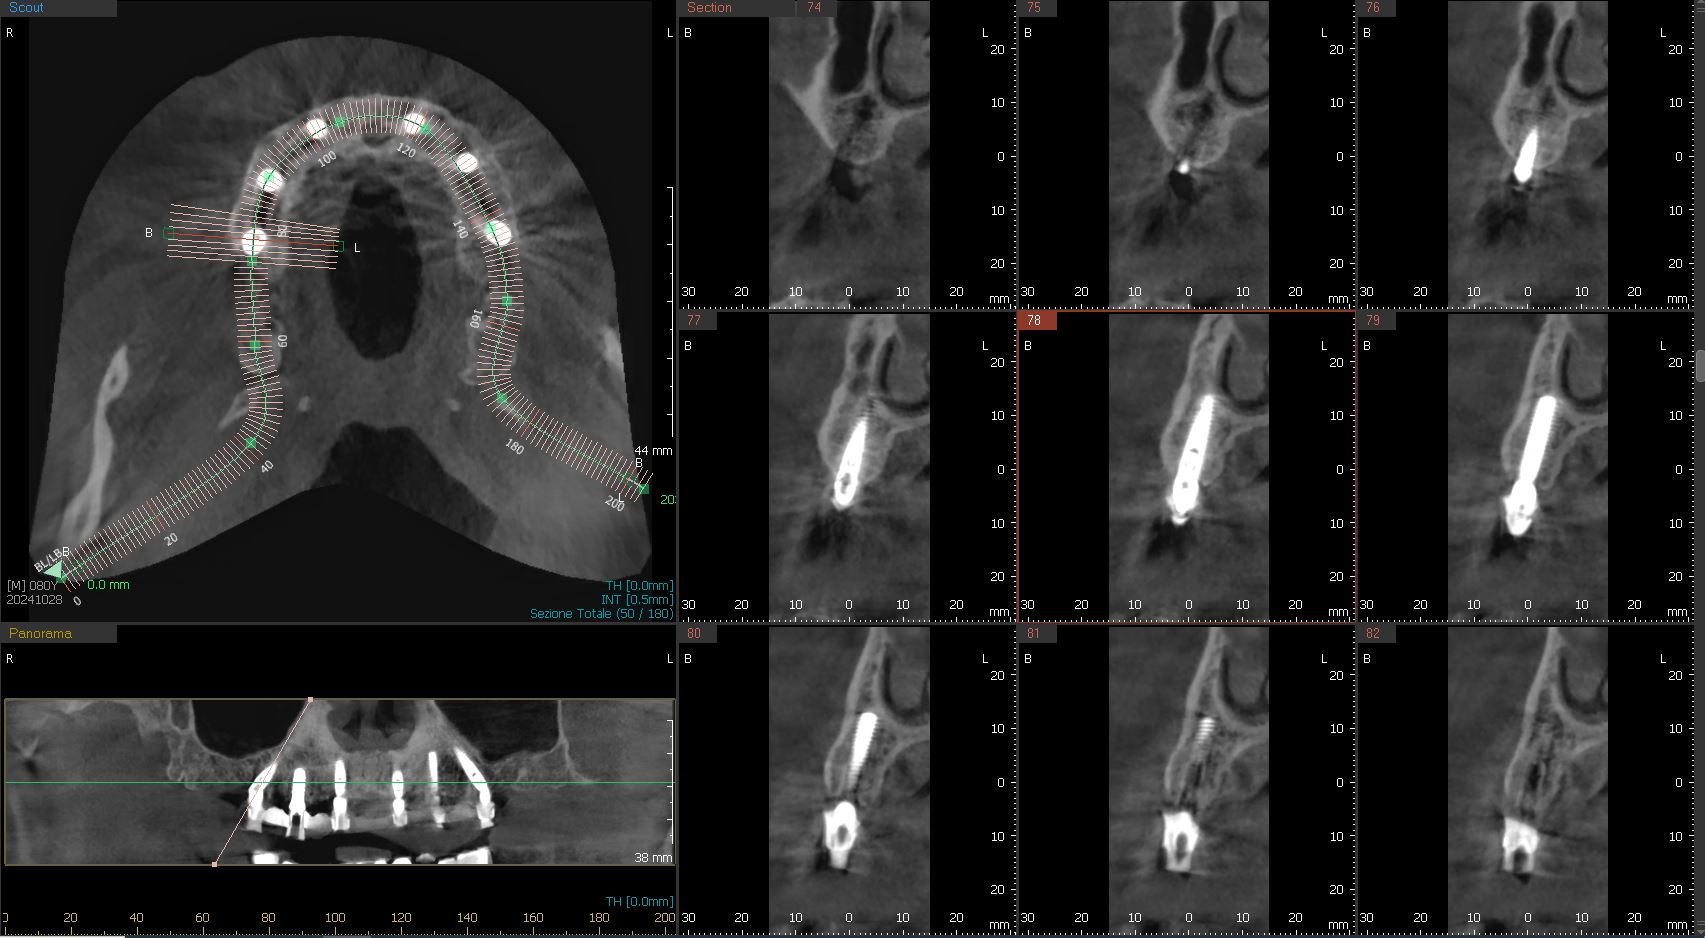

2. Pianificazione digitale avanzata

Le immagini raccolte vengono caricate in un software di pianificazione che ricrea un modello tridimensionale della bocca del paziente. In questa fase, il dentista può definire con estrema precisione il numero e la posizione degli impianti, nonché l’orientamento, la lunghezza ed il diametro con cui dovranno essere inseriti. La pianificazione prevede anche la realizzazione della protesi provvisoria, che verrà posizionata subito dopo gli impianti.

Esempio di pianificazione dell’impianto (in verde)

Esatta corrispondenza dell’inserimento implantare

Nella proiezione tridimensionale della foto di destra si nota in alto a sinistra il posizionamento dei sei impianti nello spessore osseo, in basso a sinistra gli impianti visti in posizione frontale, sulla destra le nove sezioni ossee con l’impianto visto da proiezione laterale.